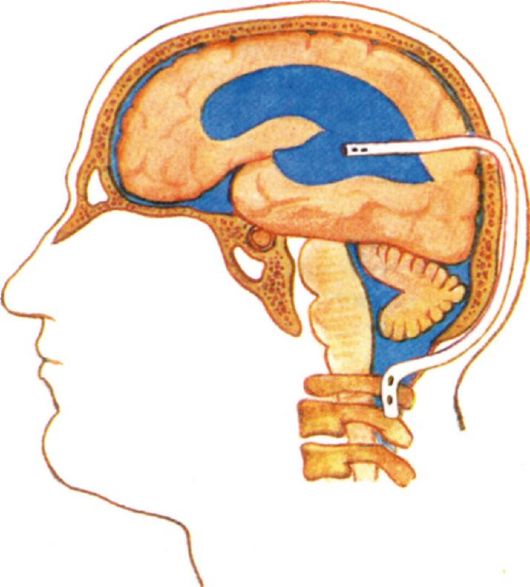

Вентрикуло-перитонеальный шунт: Показания и применение

Раздел: Фотоальбом решений